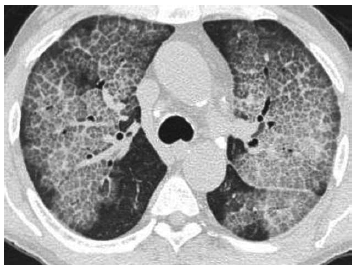

Homem de 50 anos, com dispneia há mais de 6 meses. Nesse caso, considerando-se a imagem a seguir, o padrão tomográfico e o principal diagnóstico diferencial são: